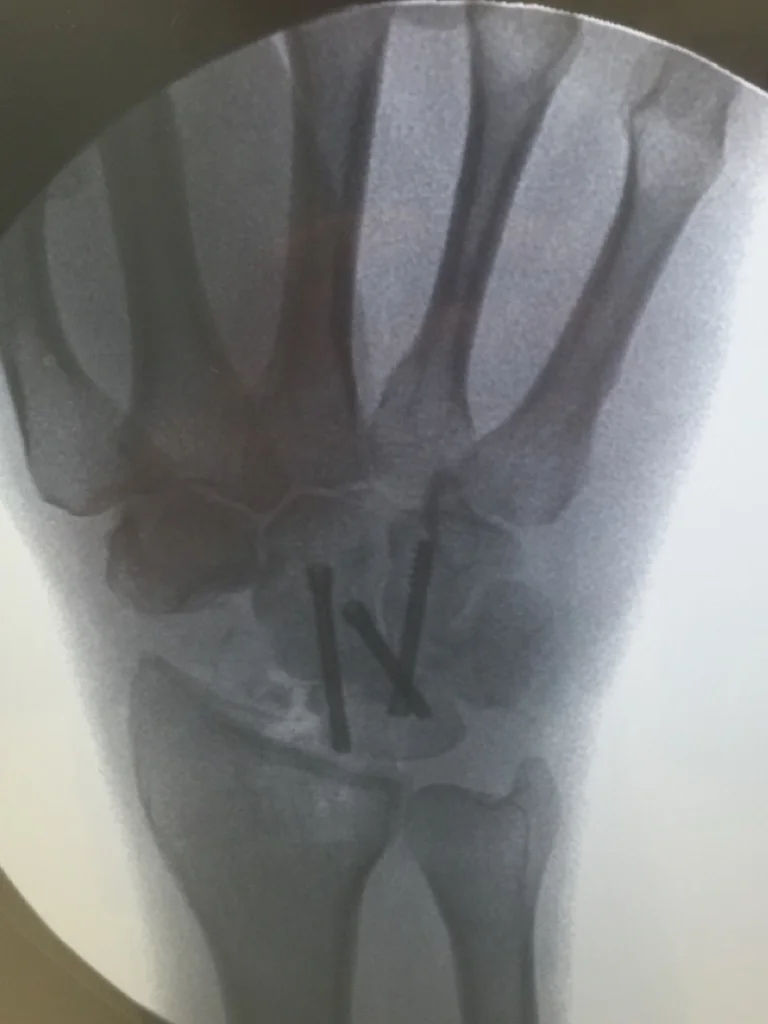

Comprehensive Orthopaedic Hand Surgery practice in Chicago's North Shore.